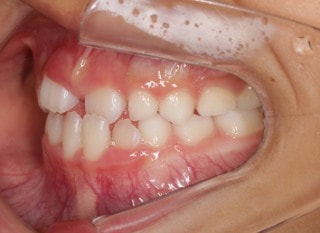

小児期の第二段階

治療中